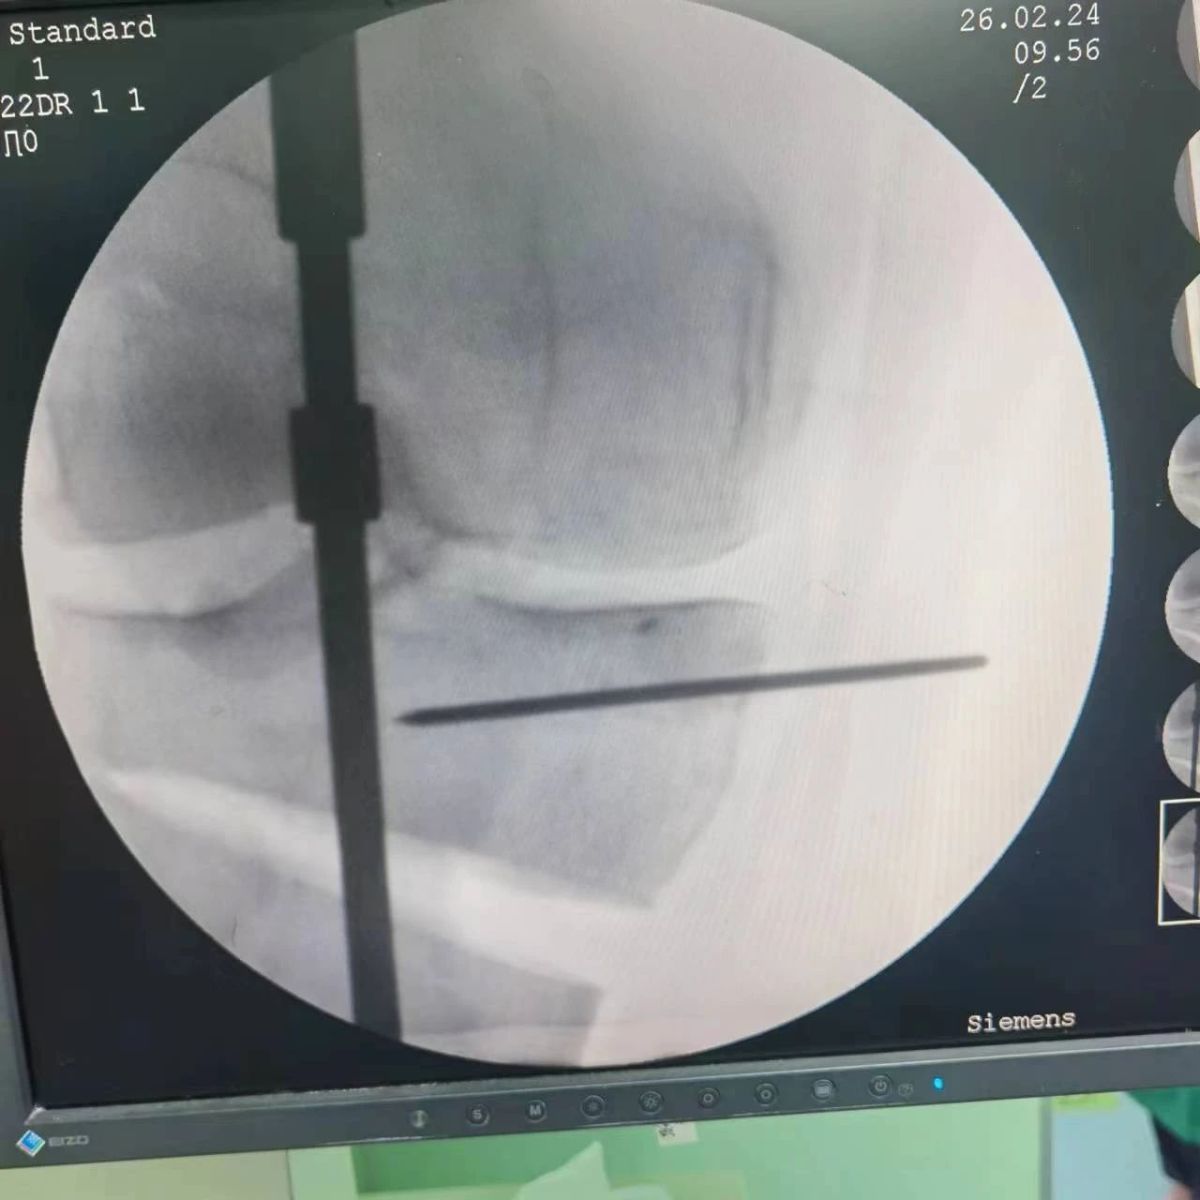

2月26日,漯河市骨科醫(yī)院(漯河醫(yī)專二附院、漯河市立醫(yī)院)膝關(guān)節(jié)外科、運動損傷科(骨六科)在保膝治療方面取得了新的突破,李付彬主任帶領(lǐng)岳龍等團(tuán)隊醫(yī)師,順利完成“計算機(jī)精準(zhǔn)術(shù)前規(guī)劃聯(lián)合3D打印截骨導(dǎo)板輔助脛骨高位截骨治療膝關(guān)節(jié)骨性關(guān)節(jié)炎”的手術(shù),這在漯河市尚屬首例!

患者為一名45歲男性,查體及X片可見明顯的膝內(nèi)翻,內(nèi)翻畸形主要來源于脛骨近端,關(guān)節(jié)鏡下可見內(nèi)側(cè)間室軟骨全層磨損,疼痛較重,年紀(jì)輕輕幾乎喪失工作能力。對于這種日?;顒有枨蟊容^大的患者朋友,我們盡最大可能給予保膝治療,李付彬主任給患者詳細(xì)講解了保膝治療的方案(脛骨近端高位截骨)及預(yù)期效果,給患者帶來了極大希望。為了更精確、更微創(chuàng)的治療,李付彬主任團(tuán)隊緊跟國內(nèi)外科技前沿,采用計算機(jī)精準(zhǔn)術(shù)前規(guī)劃,并設(shè)計3D打印截骨導(dǎo)板,力求給患者帶來更精準(zhǔn)、更安全的手術(shù)效果。

李付彬主任團(tuán)隊通過精準(zhǔn)術(shù)前規(guī)劃,設(shè)計目標(biāo)力線及調(diào)整撐開角度,轉(zhuǎn)化成需要撐開的高度,最終設(shè)計出同等高度的填充塊,術(shù)中驗證力線調(diào)整與術(shù)前規(guī)劃完全一致!

鋼板位置、螺釘位置及長度均可通過術(shù)前規(guī)劃計算,術(shù)中通過定位操作,基本與術(shù)前規(guī)劃一致,手術(shù)快速高效完成,外側(cè)合頁保留完整。無任何并發(fā)癥出現(xiàn)。術(shù)后見鋼板位置及力線糾正近乎完美!

OWHTO手術(shù)效果依賴于多個數(shù)據(jù)參數(shù),比如:截骨的入點、合頁位置的選擇、截骨線的深度、截骨線的方向、撐開的距離等,依托計算機(jī)術(shù)前精準(zhǔn)規(guī)劃和3D打印導(dǎo)板可輔助醫(yī)生精準(zhǔn)控制上述參數(shù),使截骨更準(zhǔn)確,真正達(dá)到精確的力線調(diào)整,減少術(shù)中透視次數(shù),縮短手術(shù)時間并降低手術(shù)風(fēng)險,從而使得OWHTO得到更好的應(yīng)用,造?;颊?。